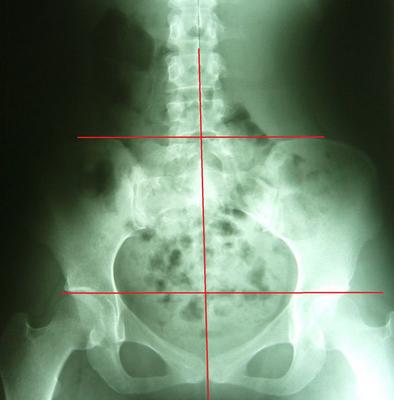

理想骨盆相对位置:两边骨盆、股骨头对称等高、中线穿过腰椎荐椎与耻骨联合、骨盆环显现对称心形